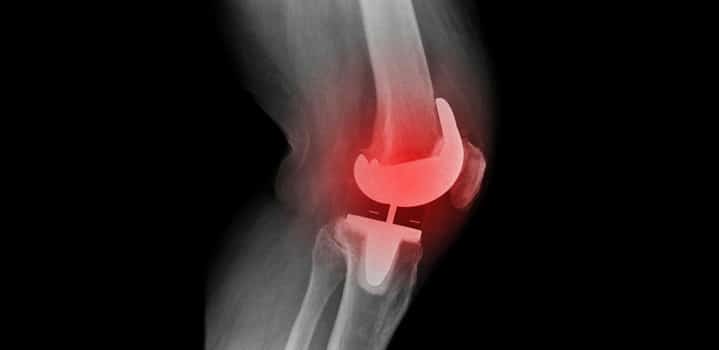

مشکلات سیستمی از جمله شل‌شدن پروتز

مشکلات سیستم حتی با ادامه پیشرفت مواد و همچنین تکنیک‌های جراحی، سطوح کاشته شده ممکن است فرسوده شوند و اجزای پروتز شما شل و شل شوند. همچنین، اگرچه به طور کلی خم‌شدن ۱۱۵ درجه زانوی شما پس از جراحی انتظار می‌رود، گاهی اوقات ممکن است جای زخم در زانو ایجاد شود که باعث محدودشدن حرکت می‌شود، به خصوص در بیمارانی که قبلاً قبل از جراحی حرکت بسیار محدودی داشتند.

• به طور دوره‌ای برای معاینه و عکس‌برداری با اشعه ایکس، معمولاً سالی یک بار، به جراح ارتوپد خود مراجعه کنید.